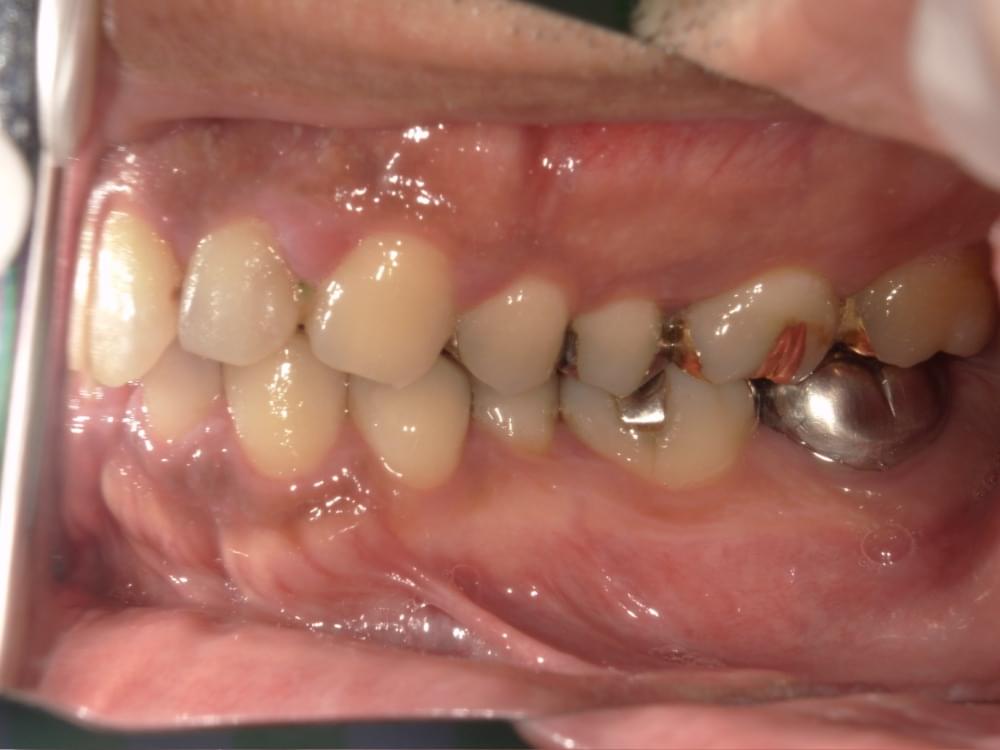

歯周病治療プログラムの治療例6

治療の概要

治療内容

行動科学に基づき、「自分の歯は自分で守る」という意識改革や行動変容を促しながら、スケーリングや歯ブラシ・フロス指導を行いました。

治療期間・回数・時間

1.5ヶ月・5回・計5時間

費用

29,500円+税

リスク・副作用

歯肉の痛み・出血